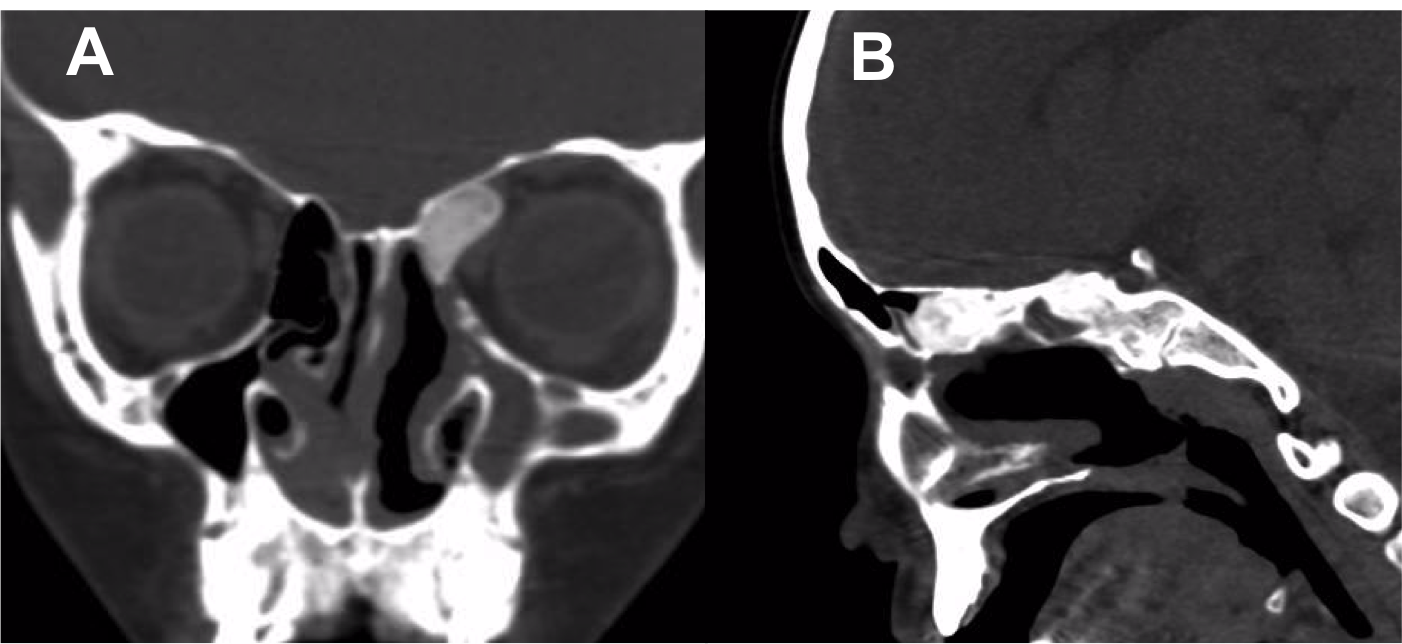

Introducción: La cirugía endoscópica endonasal se ha convertido en una herramienta fundamental para el manejo de patologías que comprometen la base de cráneo. En casos bien seleccionados, estas técnicas permiten resecciones quirúrgicas con una menor morbilidad sin comprometer los principios oncológicos de resección. Con el desarrollo de instrumental especializado, nuevas tecnologías y la experiencia de los cirujanos, la cirugía endoscópica endonasal se usa cada vez más en cirugía de base de cráneo en niños.

Diseño: Estudio observacional descriptivo de tipo serie de casos. Metodología: se describe la experiencia con pacientes pediátricos llevados a cirugía endoscópica endonasal para manejo de tumores de base de cráneo en el Instituto Nacional de Cancerología entre julio de 2014 y diciembre de 2016.

Resultados: Fueron intervenidos 8 pacientes entre los 2 y 14 años, con una edad promedio de nueve años y un seguimiento promedio de 16 meses. En el 75% se hizo una resección total del tumor. Un paciente requirió una reintervención y un paciente fue sometido a radiocirugía post-operatoria. 1 paciente falleció a pesar de múltiples intervenciones, quimioterapia y radioterapia.

Conclusión: La cirugía endoscópica endonasal para tumores de base de cráneo puede ser utilizada de forma segura en los pacientes pediátricos, es una técnica que en casos bien seleccionados pueden ofrecer excelentes resultados disminuyendo la morbilidad y complicaciones de las técnicas abiertas.

Banu MA, Rathman A, Patel KS, Souweidane MM, Anand VK, Greenfield JP, et al. Corridor-based endonasal endoscopic surgery for pediatric skull base pathology with detailed radioanatomic measurements. Neurosurgery. 2014;10(2):273–93.

Shah RN, Surowitz JB, Patel MR, Huang BY, Snyderman CH, Carrau RL, et al. Endoscopic pedicled nasoseptal flap reconstruction for pediatric skull base defects. Laryngoscope. 2009;119(6):1067–75.